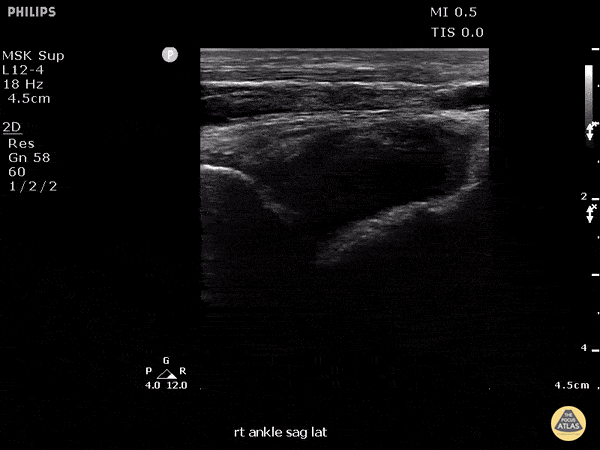

This patient presented to the emergency department for several days of ankle pain. Ultrasound of the joint revealed anechoic fluid within the joint, which normally suggests a non-exudative cause. However, this patient’s joint was eventually tapped which revealed thick purulent fluid that grew Fusobacterium, and a rare cause of septic joint. Image courtesy of Robert Jones DO, FACEP @RJonesSonoEM Director, Emergency Ultrasound; MetroHealth Medical Center; Professor, Case Western Reserve Medical School, Cleveland, OH View his original post here